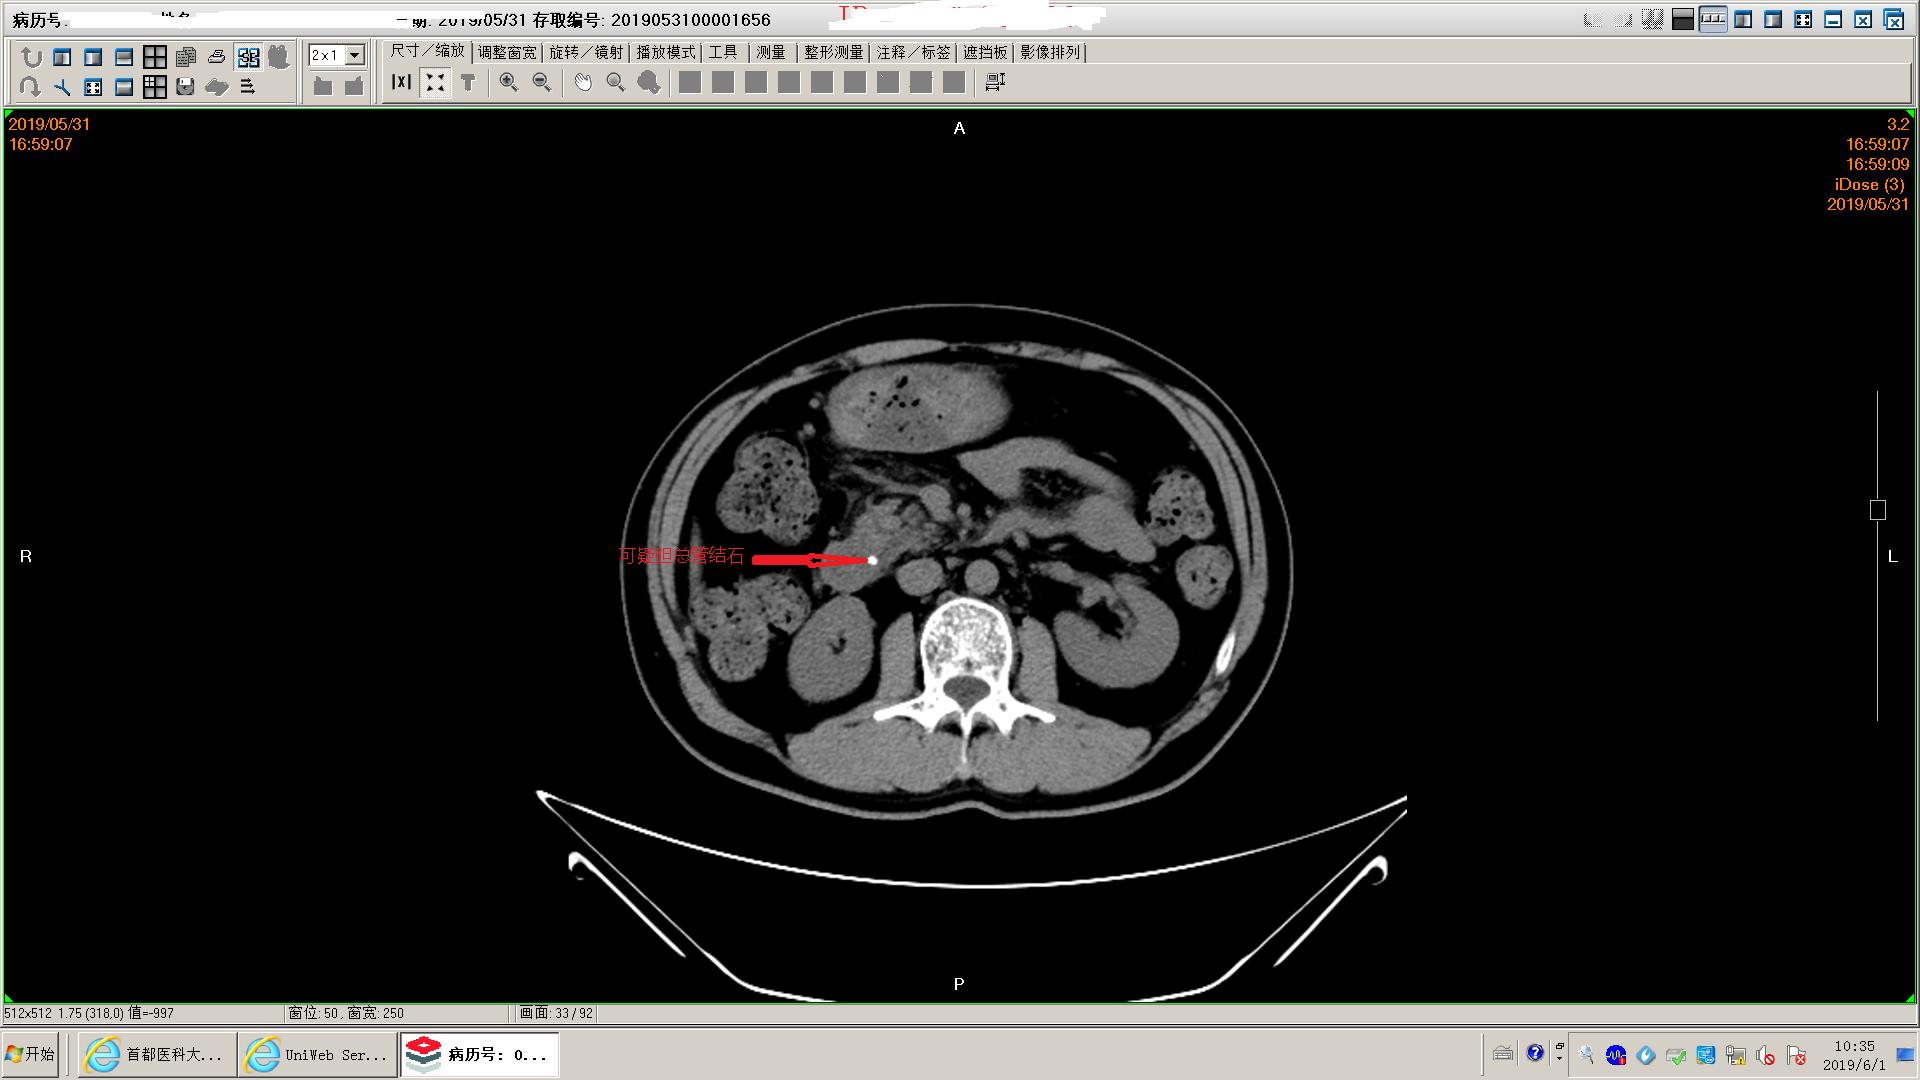

下面是一例胆源性胰腺炎影像学和化验表现,这个病人没有脏器功能不全,胰腺坏死不明显,周围没有明显积液,还不是重症胰腺炎。虽然有可疑胆管结石,但是没有黄疸,我们会在做核磁mrcp证实一下结石的位置。患者胃里面有一些残存的食物,我们会用胃管做胃肠减压,有助于胃肠道休息恢复;肠道里面积存的粪便也比较多,肠鸣音听不到,通过肥皂水灌肠促进肠道蠕动排除,有助于胃肠道功能恢复。然后给予生长抑素抑制胰酶分泌,禁食水补液,消炎治疗。

可疑胆总管结石